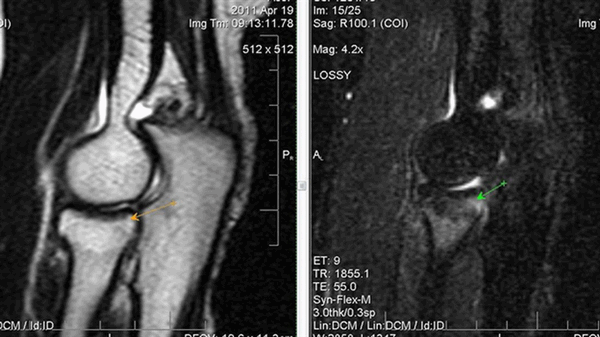

Патологии локтевого сустава на МРТ

МРТ картина синовита, стрелками указаны участки отека костной ткани локтевого отростка

Особенность обследования заключается в четком отражении без облучения не столько костных образований, сколько мягких тканей. МРТ локтевого сустава покажет, что именно изменено в его строении. Доктор сможет определить по снимку патологические изменения:

- воспаление суставной сумки (бурсит), сухожилий (тендинит), связок (лигаментит) и пр.;

- гнойное поражение костей (остеомиелит);

- перелом;

- вывих;

- сужение суставной щели;

- повреждения хрящей;

- артрит и артроз;

- доброкачественные и злокачественные опухоли и пр.